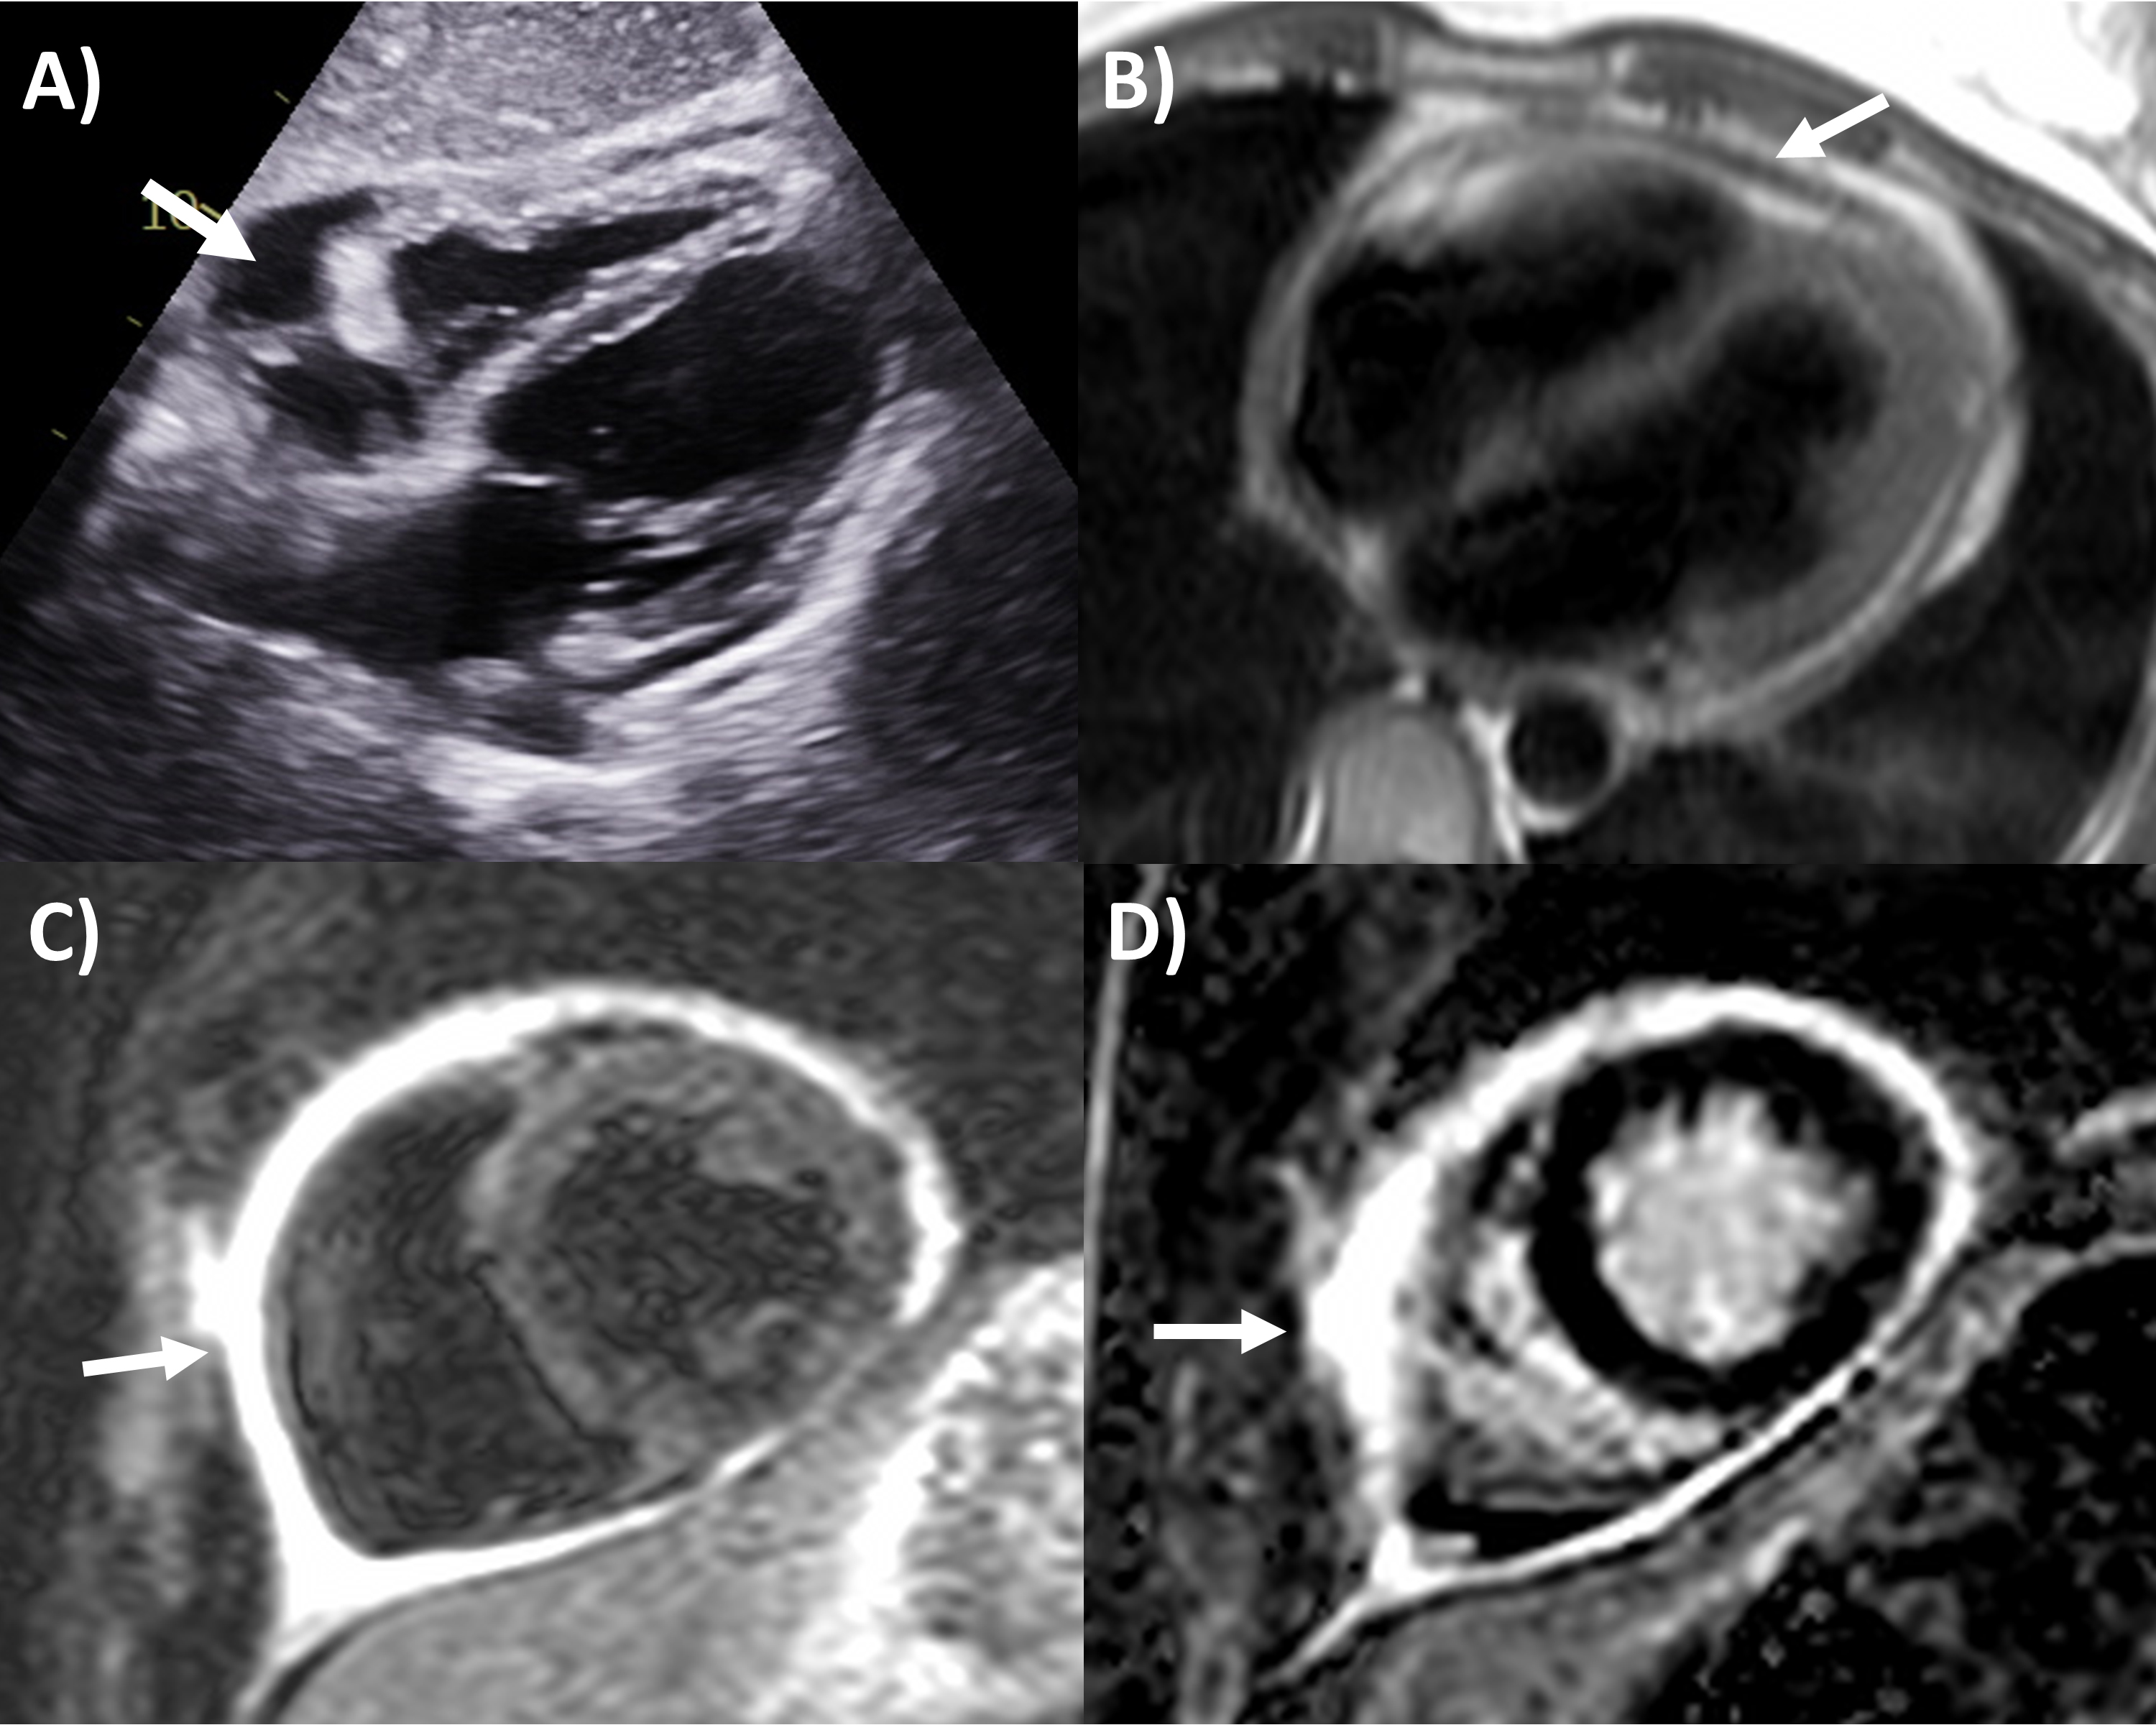

CT has greater ability for tissue characterization than echocardiography, and is able to assess the extent, local or distant spread of masses, lymph node involvement and many pericardial tumors have associated effusions that are hemorrhagic or exudative [31]. Hemangiomas appear heterogenous with contrast enhancement; lymphangiomas are heterogenous with low attenuation and septae; lipoma have low fat-level attenuation that is circumscribed, and sometimes can surround coronary arteries; teratomas usually have contain areas of calcification and fat; lymphoma are hypoattenuating with contrast enhancement; fibromas are homogeneous with no or minimal enhancement given lack of vascularity; sarcomas are broad-based masses which invade adjacent structures; and mesothelioma is seen as diffuse irregular pericardial thickening with effusion [31, 56]. Pericardial cysts are seen as a well-circumscribed homogeneous mass with thin wall on CT, with fluid density, unaffected by intravenous contrast (Fig. 4) [59, 60].

Fig. 4.Multi-modality imaging tissue characterization of pericardial cyst (arrows in all panels) adjacent to the right atrium. (A) Computed tomography axial slice, cyst was 10 Hounsfield units. (B) Magnetic resonance imaging (MRI) steady-state free precession bright blood sequence axial slice, cyst has increased signal. (C) MRI T2-short tau inversion recovery sequence, cyst has high signal. (D) MRI late gadolinium enhancement sequence axial slice, cyst has low signal.

MRI’s main advantage amongst imaging modalities is its ability in tissue characterization, and this is no different when applied to pericardial masses. Depending on tumor extension, the pericardium or myocardium may show thickening, or pericardial effusions, the latter often exudative or hemorrhagic with high signal intensity on T1-weighted sequences [31]. On T1-weighted, T2-weighted and gadolinium enhanced sequences, many tumors have low, high and high signal intensities [14, 31, 61, 62, 63]. Hemangiomas generally appear heterogeneous on all sequences, while lipomas have high signal intensity on all sequences, however its signal can be uniquely suppressed on fat-saturation pulse sequences. Fibroma have low vascularity and therefore have low signal intensity on T2-weighted sequence and none to minimal enhancement on gadolinium enhanced sequences. Mesotheliomas appear homogeneous on T1-weighted but have heterogenenous elevated signal on T2-weighte and gadolinium enhanced sequences. Of note, some studies have suggested heterogenous gadolinium uptake to indicate areas of increased lesion nodularity, growth and/or necrosis [64]. Pericardial cysts also appear as a well-circumscribed homogeneous mass with thin wall on MRI, displaying hypointense signal on T1-weighted sequence unless there is an exudative or hemorrhagic component, with hyperintense signal on T2-weighted sequence and no signal on LGE sequence (Fig. 4) [31, 65]. Lastly, pericardial hematomas show hyperintense, heterogeneous and hypointense signal on T1 and T2 weighted sequences in the acute, subacute and chronic stages, and no signal on LGE sequences regardless of timeframe [31].